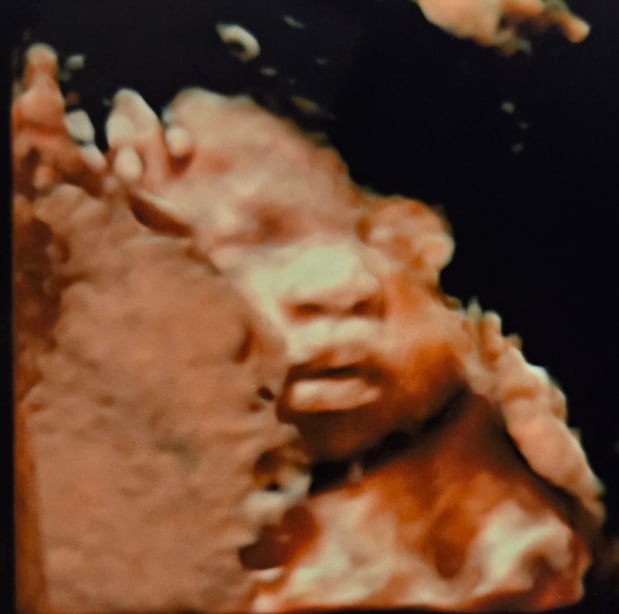

Tasha Crump, is registered by the American Registry of Diagnostic Medical Sonographers (ARDMS) and have over 18 years experience in medical diagnostic sonography specializing in Maternal Fetal Medicine. She is a highly proficient in the art of 3D 4D ultrasound. Tasha has practiced and trained in NYC's top ranked hospitals including Columbia Presbyterian. At Love at First Sight Imaging Studio you'll be in a very comfortable and calming atmosphere for you and your family to bond with your baby. We have state of the art equipment with HD Live to image unbelievably realistic views of your baby. You will fall in Love at First Sight.